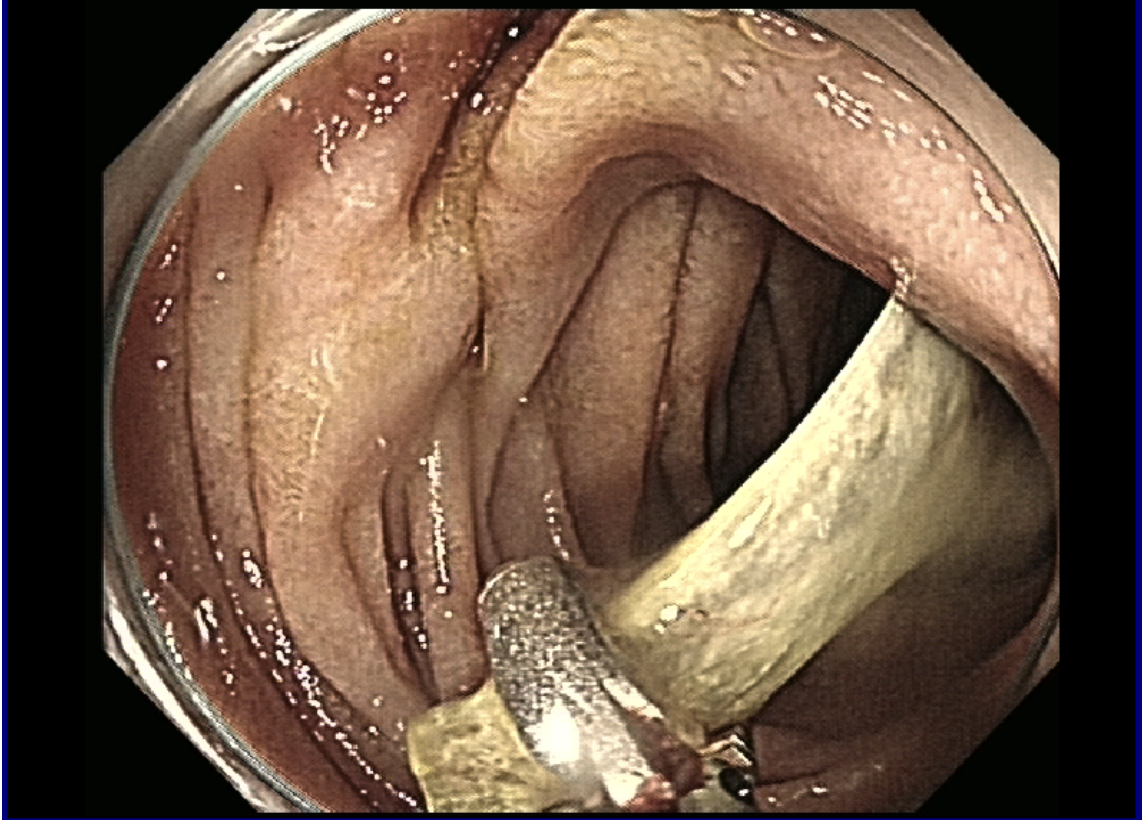

内镜下异物钳取异物。

面对这一棘手情况,北院内镜诊疗团队结合影像学检查结果对病情进行周密评估,精准判断羊骨嵌顿角度、与肠壁贴合程度及周边组织情况,制定了个性化的微创取出方案;麻醉科充分术前评估,为手术顺利进行保驾护航;普外科医师随时待命。手术在多科室密切配合下进行。专家团队全程操作轻柔精准,进镜发现骨头已造成十二指肠深溃疡,万幸未发现活动性出血。先通过专业器械稳妥固定羊骨,小心松解其与肠壁的粘连,避免直接牵拉造成肠壁撕裂;随后调整羊骨角度,使其与消化道走行保持平行,缓慢将其尖锐部位拉入透明帽中,成功取出嵌顿的羊骨。手术全程微创无开刀,未对肠壁黏膜造成损伤。